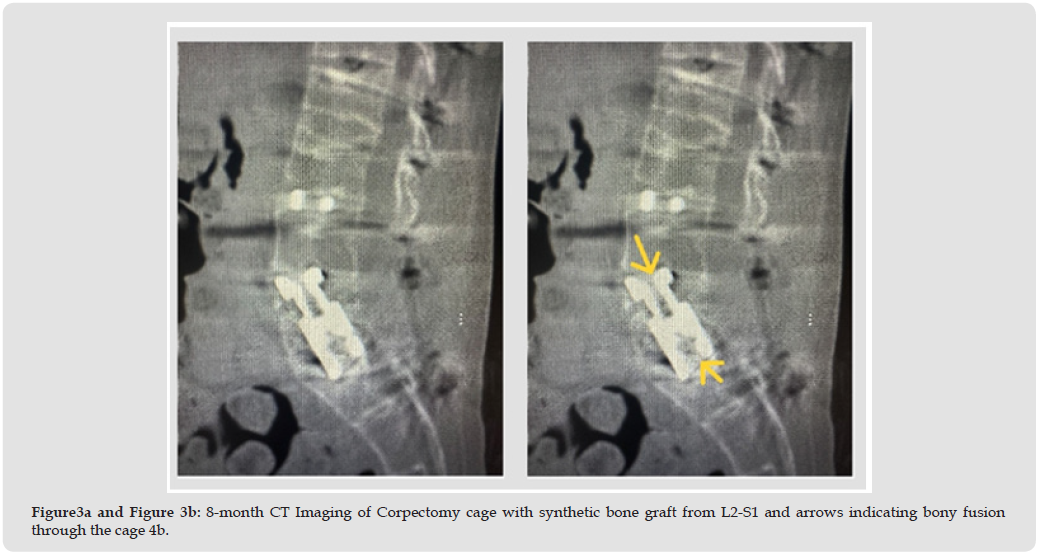

The patient is a 36-year-old male (BMI 18) with a history of ongoing intravenous drug abuse presenting with severe spinal deformity, inability to stand upright, and protracted pain. The patient’s disability has progressed to the point of inability to perform activities of daily living. On physical examination, the patient demonstrates approximately 60 degrees of lumbar which is rigid on range of motion testing. Weakness of the bilateral quadriceps, anterior tibialis and gastrocnemius is present on manual muscle testing. Lumbar CT imaging is significant for severe destruction of the L3, L4 and L5 vertebral bodies (Figures 1a & 1b). The patient was indicated for 3-level lumbar corpectomy from a posterior approach with fixation from T10 to pelvis. Intraoperative cultures were positive for methicillin-resistant Staphylococcus aureus. A titanium corpectomy cage filled with (Sur- GenTec Osteoflo® Hydrofiber) (Figure 2) was placed from L2 to S1 for anterior column stabilization (Figure 3a). Osteoflo® Hydrofiber was reconstituted with saline only and used stand-alone. Postoperative x-ray (Figures 4a & 4B) imaging confirmed appropriate deformity correction and CT imaging at 8 months confirmed fusion (Figure 3b) from L2-S1 through the corpectomy cage.

Procedure: Posterior approach L2–S1 reconstruction, including three-level lumbar corpectomy and fixation from T10 to pelvis. Intraoperative cultures were positive for MRSA. A titanium corpectomy cage was filled entirely with Osteoflo® Hydrofiber, reconstituted with saline.

Outcome: Postoperative imaging confirmed deformity correction. At 8 months, CT demonstrated solid fusion through the corpectomy cage despite severe infection.